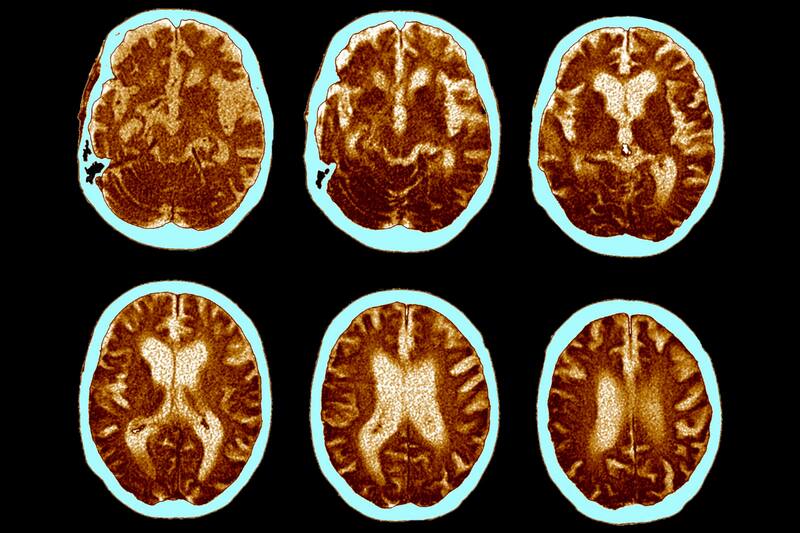

La enfermedad de Alzheimer es trastorno cerebral progresivo que gradualmente deteriora la memoria y las capacidades cognitivas, llegando eventualmente a afectar incluso las actividades más básicas de la vida diaria.

Los científicos hicieron crecer neuronas en el laboratorio usando células especiales de pacientes con Alzheimer. Estas neuronas “mini-cerebros” se usaron para estudiar cómo reacciona el Alzheimer al sildenafilo (viagra), un medicamento para la disfunción eréctil.